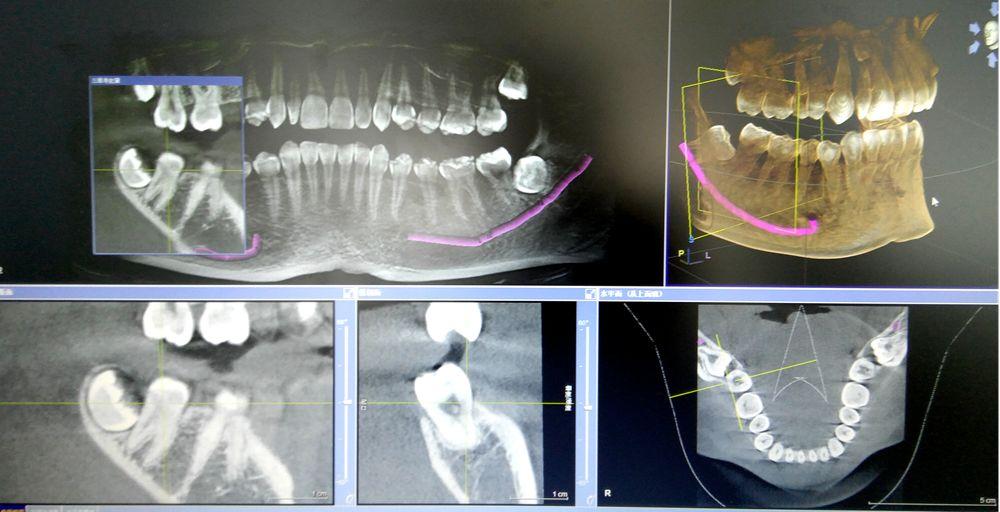

CBCT掃描可準確分析頜骨植入?yún)^(qū)的骨質(zhì)、骨量、骨密度及植體與下頜神經(jīng)管、上頜竇的關(guān)系,臨床醫(yī)生可以在圖像上模擬種植,直接與患者進行溝通及交流,并可指導手術(shù)者在手術(shù)方案中避開危險區(qū)域,手術(shù)的性。此外,臨床醫(yī)生還可以利用CT數(shù)據(jù)進行數(shù)字模型重建,配合軟件預(yù)先做好手術(shù)模板使種植手術(shù)更快捷。